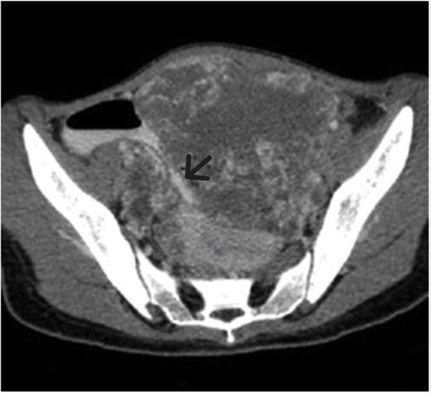

A 7year old prepubertal amenorrhoeic girl presented in March 2023 at our OPD with a history of lower abdominal pain and swelling for past 3 months, which were progressive in nature. She was admitted in the emergencies with a history of Acute Abdomen. CECT of Whole Abdomen done on 20/04/2023, it shows 14x12x9 cm large Heterogeneous enhancing solid lesion in mid, lower abdomen and pelvis compressing the bowel loops with proximal small bowel obstruction. Blood reports on 16/04/2023, AFP- 213, LDH- 2194, BetaHCG- 4145, CA-125: 96.7, CEA- 0.71, CA 19-9: 21.2

Figure 1: CECT scan of Pelvis (preoperative) showing a pelvic SOL compressing Bowel loops (arrow).